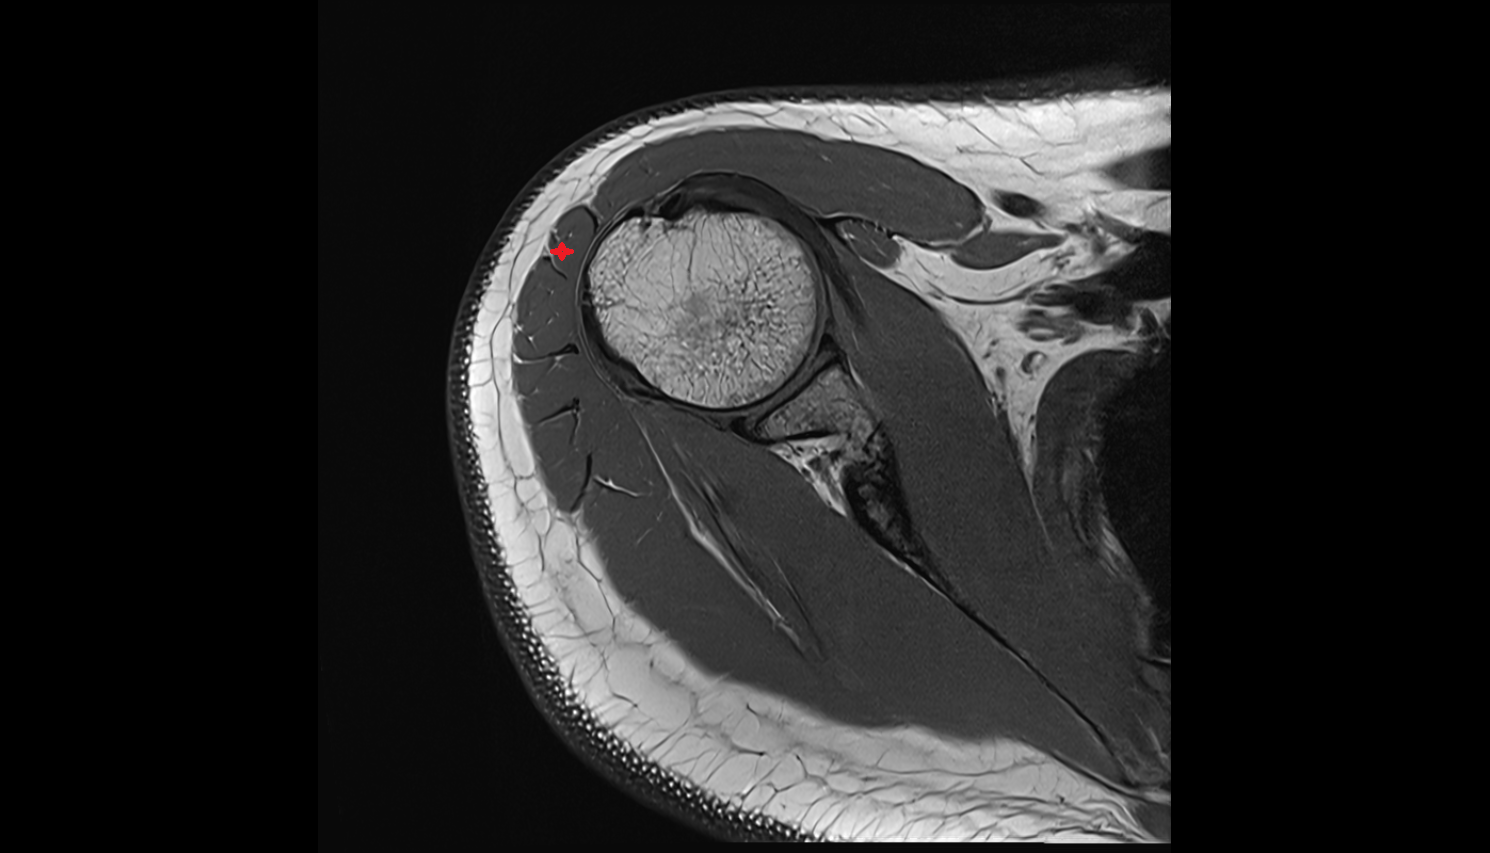

- Shoulder joint (glenohumeral joint)